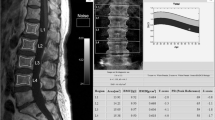

First, a real-time phantom consisting of oil and water tubes was manufactured. Then, 30 female volunteers (age: 62.3 ± 6.3 years) underwent lumbar spine examination with MRI (using a novel phantom) and dual-energy X-ray absorptiometry (DXA), following ethical approval. MRI phantom-based F-score and W-score were defined by normalizing the vertebral signal intensities (SIs) by the oil and water SIs of the phantom on T1- and T2-weighted images, respectively. The diagnostic performances of the new scores for assessing osteoporosis and vertebral fractures were examined using receiver operating characteristic analysis and compared with DXA-measured areal bone mineral density (DXA-aBMD).

The F-score and W-score were greater in the osteoporotic patients (3.93 and 2.29) than the non-osteoporotic subjects (3.05 and 1.79) and achieved AUC values of 0.85 and 0.74 (p < 0.05), respectively, when detecting osteoporosis. Similarly, F-score and W-score had greater values for the fracture patients (3.94 and 2.53) than the non-fracture subjects (3.14 and 1.69) and produced better AUC values (0.90 for W-score and 0.79 for F-score) compared to DXA-aBMD (AUC: 0.27, p < 0.05). In addition, the F-score and W-score had a strong correlation (r = 0.77; p < 0.001).

A novel real-time lumber spine MRI phantom was developed, based upon which newly defined F-score and W-score were able to detect osteoporosis and demonstrated an improved ability over DXA-aBMD in differentiating patients with vertebral fractures.